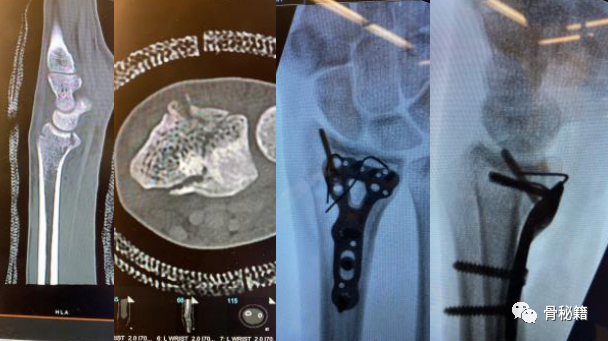

介绍几种可以应用的固定方式,掌侧支持克氏针和及远端的勾钢板。

掌侧的一个边缘剪切骨折伴有脱位,采用边缘克氏针固定。

可见骨折固定良好,关节稳定

掌侧勾钢板固定骨折块